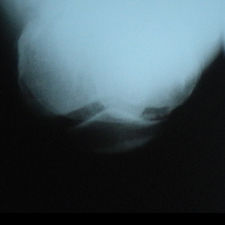

A 58 year old, male patient presented with a history of left knee pain and loss of function over 4 years.

On clinical and radiological examination, he was assessed as having Medial Compartment Osteoarthritis. A uni-compartmental knee replacement was recommended and performed in June 2011. Patient has gone onto complete recovery with a satisfactory clinical outcome. She returned to independent function, six weeks after the surgery and now has an pain-free existence with full function in the right knee after two months.